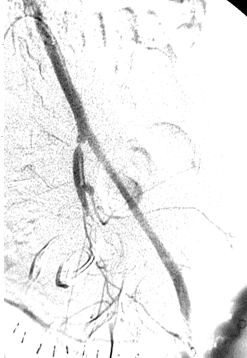

所有年龄超过 40 岁的患者, 卵巢受损 14%-43% 研究中闭经发生率(15%)与单纯UAE报告相似,可能与患者年龄(≥45岁)及卵巢储备自然下降有关。 ![]() 50岁,长期因子宫肌瘤导致月经出血过多,痛经和贫血。 子宫肌瘤栓塞术前,显示双侧子宫动脉发育不全,子宫肌瘤双侧卵巢动脉。 经皮股动脉穿刺双侧卵巢动脉栓塞,先500μm-700μm emboSphere 微球 术后4周,和6月的中短期随访,月经正常,子宫容积减少,贫血纠正,无卵巢功能衰竭。但看起来非灌注容积较少。 术后9月,由于子宫肌瘤持续存在,患者自己希望绝经,行全子宫和双侧卵巢切除术 术后病理,子宫内可见栓塞微粒伴有坏死,卵巢内也见栓塞微粒,但卵巢功能未受损。